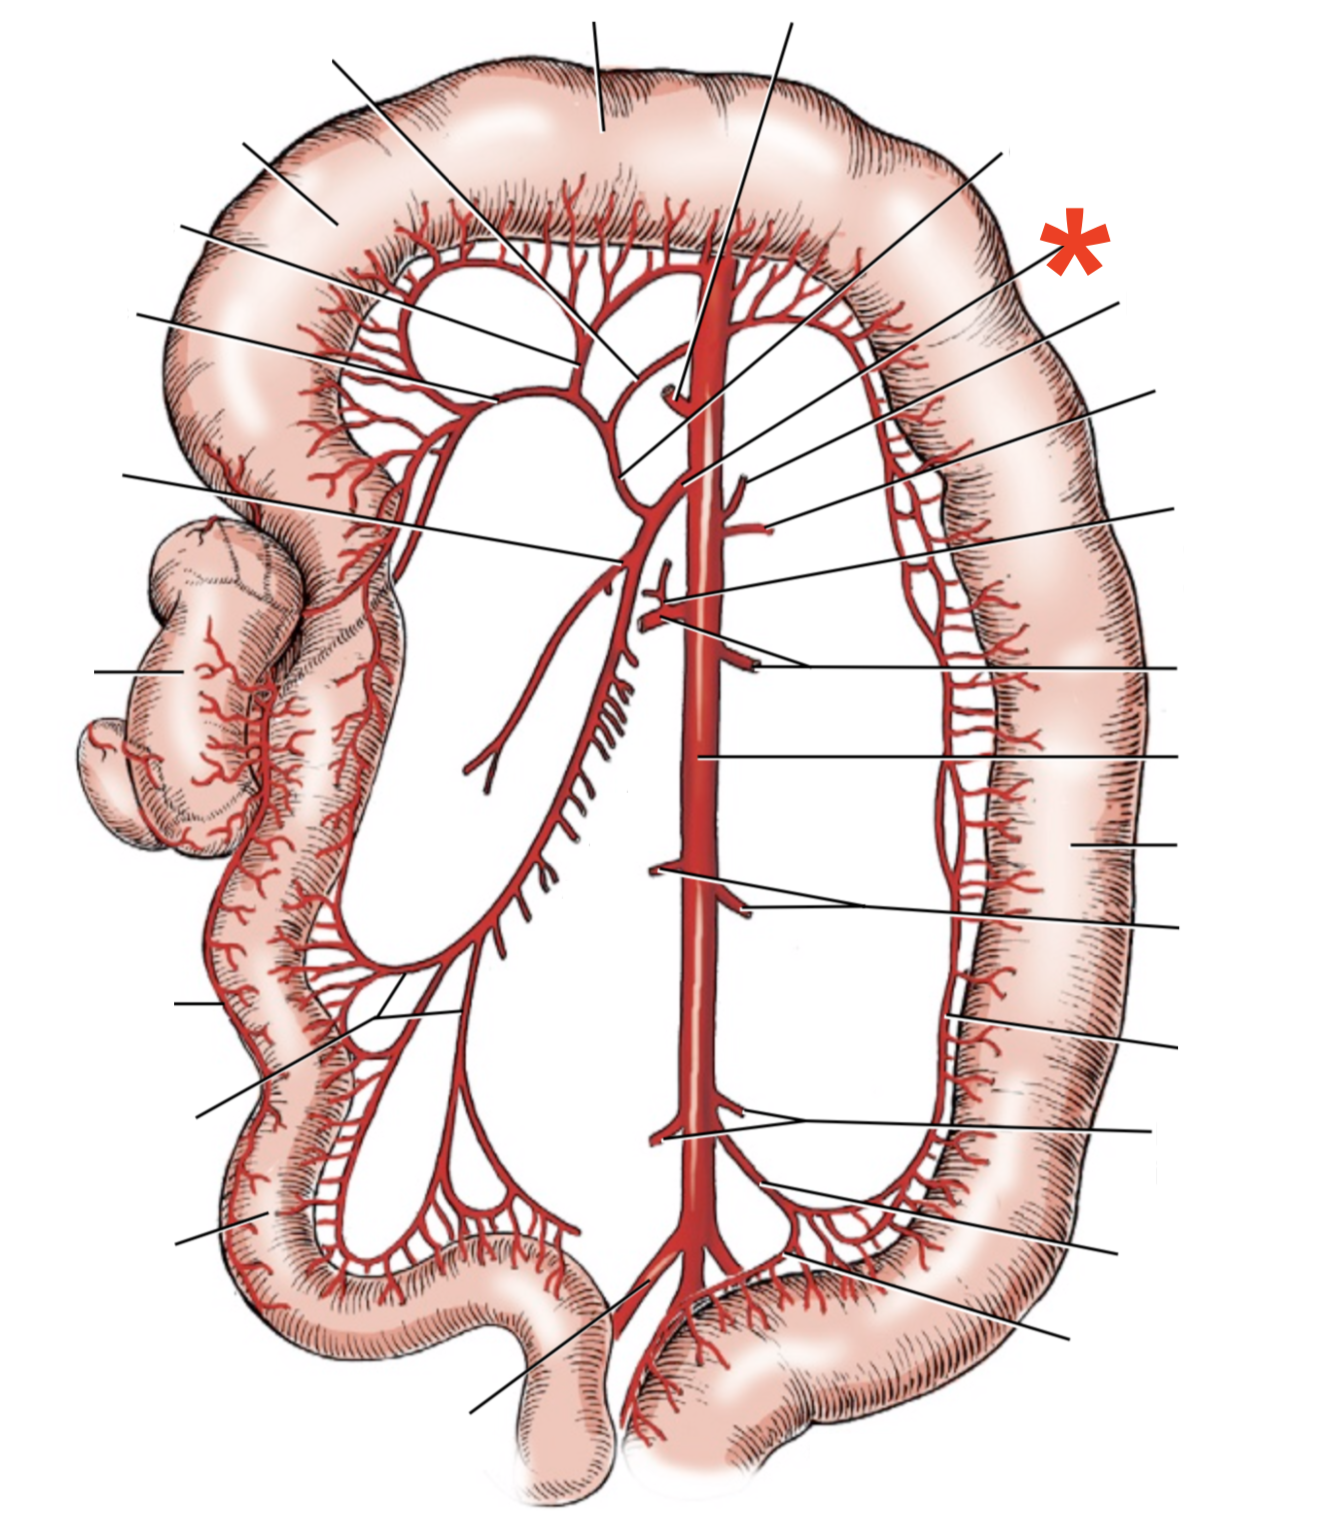

13

A

A. mesenterica cranialis

14

A

A. mesenterica caudalis

15

A

A. pancreaticoduodenalis caudalis

16

A

Aa. jejunales

17

A

A. ilei

- Anastomises with r. ileus mesenterialis a. iliocolica

18

A

A. ileocolica

19

A

A. colica dextra

20

A

A. colica media

21

A

A. mesenterica caudalis

22

A

A. colica sinistra

23

A

A. rectalis cranialis

24

A

A. ileocolica

25

**A.** **caecalis**

**R.** **ilei** **mesenterialis**

List the branching of *a.* *mesenterica* *caudalis*

* *A. colica sinistra*

* *A. rectalis cranialis*

List the branches of *a.* *mesenterica* *cranialis*

* *A.* *pancreaticoduodenalis* *caudalis*

* *Aa. jejunalis*

* *A. ilei*

* Common trunk

* A. colica media

* A. colica dextra

* *A. ileocolica*

* *R. ilei mesenterialis*

* *A. cecalis*

* *R. colicus*